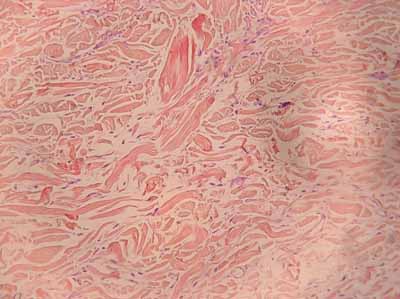

L’examen histopathologique montre le remplacement du tissu dermique par des fibres de collagène d’arrangement presque normal; une densification des fibres de collagène avec des faisceaux épais et tassés, le remplacement par un tissu fibreux des annexes folliculaires et la présence d’un infiltrat inflammatoire discret périvasculaire et périnerveux (photo 4).

Photo 4 : examen histopathologique de la lésion:

remplacement du tissu dermique normal

et des annexes par des fibres de collagène